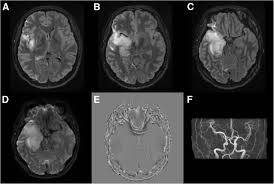

Mri is the imaging of choice in suspected cases of viral encephalitis, although ct scanning may be used where mri facilities are not available. A case of granulomatous hsv encephalitis: Hsv pcr and other infectious studies from the serum and csf were negative. Brain mri is shown in fig. Severe infection, particularly untreated herpes simplex virus (hsv) encephalitis, can cause brain hemorrhagic necrosis.

Brain mri—increased t2 signal intensity in frontotemporal region → viral (hsv) encephalitis.

In children older than 3 months and in adults brain biopsy: Herpesviral encephalitis, or herpes simplex encephalitis (hse), is encephalitis due to herpes simplex virus. • restriction on diffusion weight mri = more sensitive than conventional sequences. Misra uk, hashmi aa, kalita j. Diagnostic uncertainty and empirical management in pcr negative encephalitis. It is a severe condition brain mri may show limbic encephalitis (55) or diffuse t2 and dwi hyperintensities in the white matter, associated with restricted diffusion (54). Herpes simplex encephalitis occurs as 2 distinct entities: Mri is the imaging of choice in suspected cases of viral encephalitis, although ct scanning may be used where mri facilities are not available. The patient had initially improved after medical treatment. Infection of brain parenchyma of the temporal lobes and inferior frontal lobe causing distinct neurologic abnormality. Dhawan a, kecskes z, jyoti r, kent al. Associated with hsv encephalitis (strong evidence). In addition, because of the involvement of the.

It is a severe condition brain mri may show limbic encephalitis (55) or diffuse t2 and dwi hyperintensities in the white matter, associated with restricted diffusion (54). Brain mri—increased t2 signal intensity in frontotemporal region → viral (hsv) encephalitis. Associated with hsv encephalitis (strong evidence). Provided cranial imaging has excluded any contraindications such as a space occupying lesion or severe cerebral oedema and brain shift, a csf. Having said that, mri with contrast is considered the most sensitive imaging modality, and findings are present in over half of individuals 8. In addition, because of the involvement of the. We performed volumetric measurements of the left and right temporal lobes and of cerebral oedema. Herpes simplex encephalitis occurs as 2 distinct entities: The study analysed serially acquired magnetic resonance images (mri), of patients with acute hsv encephalitis who had neuroimaging repeated within four weeks of the first scan. Pregnancy the most common cause of encephalitis in newborns is vaginal delivery from a mother who is infected with herpes simplex virus 2 (hsv 2). There is no particular age, sex, or seasonal predilection. Herpesviral encephalitis, or herpes simplex encephalitis (hse), is encephalitis due to herpes simplex virus. Severe infection, particularly untreated herpes simplex virus (hsv) encephalitis, can cause brain hemorrhagic necrosis.